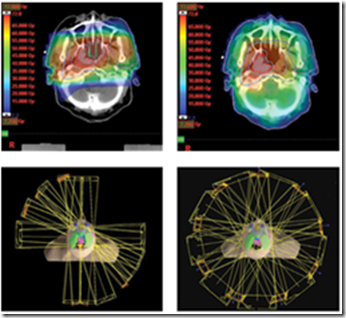

image

Medulloblastoma – affects children. Malignant brain tumour is surgically removed and afterwards, to prevent spread, you want to sterilize the spine with radiation.

A few developments